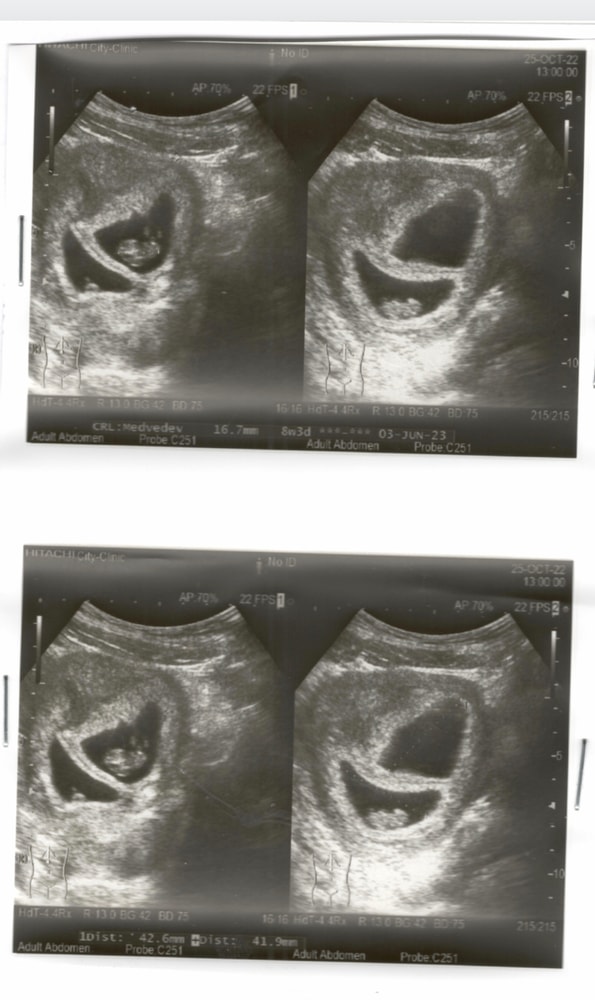

УЗИ 7 недель ди ди двойня(разнояйцевые) Изображение

Надежда , у вас да, прям очевидно разнояйцевые! А к меня все же перегородка тоньше

Эльза, они недалеко, но есть перегородка Изображение

Катя, это далеко. Просто срок у вас уже не 5 недель а больше, поэтому это расстояние вам кажется перегородкой. Это разнояйцевые или дихориальная диамниотич двойня.

Катя, мне кажется разнояйцевые, яйцам просто места мало уже, поджимаются